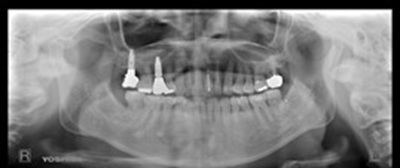

術前パノラマ![]() |

この部位では、骨がやわらかく初期の安定が得にくいことから、Zimmer社のスプラインインプラントを採用しました。このタイプはねじ山が深く、柔らかい骨でもしっかりと固定される構造になっています。骨の高さを補うためにソケットリフトを行い、骨補填材を併用して安定した支えを作りました。手術後も動揺や骨吸収は見られず、長期的に安定した状態を保っています。

手前の歯では、抜歯と同時にインプラントを埋め込む「抜歯即時埋入」を行いました。この部位では骨はしっかりしていましたが、噛む力が強く、歯ぎしりの影響を受けやすいため、高い精度で補綴物と連結でき、咬合力に強い構造を持つStraumann社のボーンレベルSLActiveを選択しました。このインプラントは表面が特殊に処理されており、骨との結合が非常に速く進む特徴があります。骨補填材(Bio-Oss、コラプラグ)を併用し、術後は軽度の出血が見られましたがすぐに落ち着き、治癒は良好でした。

本埋入後4か月で最終的な被せ物を装着しました。咬み合わせを調整し、ナイトガードを使用して就寝時の負荷を軽減しました。現在も4か月ごとのメインテナンスを継続しており、インプラントと周囲の歯ぐきは安定しています。骨質や噛む力、部位ごとの条件に合わせてインプラントを使い分けることが、長く良い状態を保つために大切だと改めて感じました。